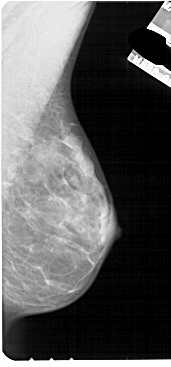

A_1841_1.RIGHT_MLO

RIGHT_MLO LINES 5491 PIXELS_PER_LINE 2551 BITS_PER_PIXEL 12 RESOLUTION 43.5 NON_OVERLAY